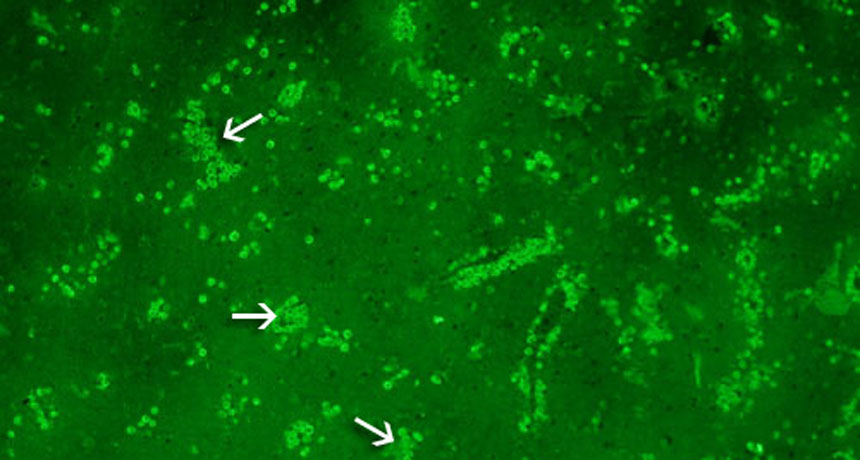

This section of brain came from a patient infected with N. fowleri. A fluorescent stain highlights, under the microscope, the tiny amoebas as bright green dots. Arrows point to some large clusters of them.

CDC